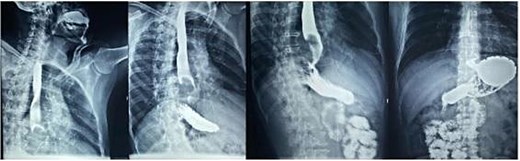

Endoscopic biopsies were negative immunostaining for DOG1 and CD117, ruling out a GIST, but positivity for actin with nuclear atypia, suggesting a smooth-muscle tumor of uncertain malignant potential. Contrast-enhanced computed tomography (CT) scan (Fig. 3) showed a 67 × 51 × 47 mm lobulated intraesophageal lesion with central necrosis and strong enhancement, originating from the posterior esophageal wall and nearly occluding the lumen, without regional lymphadenopathy, local invasion, or metastases.

Contrast-enhanced thoracoabdominopelvic CT scan: (a) axial section showing an oval intraesophageal mass; (b) coronal section illustrating the longitudinal extent of the tumor; (c) sagittal section showing a tumor apparently respecting the pericardium.